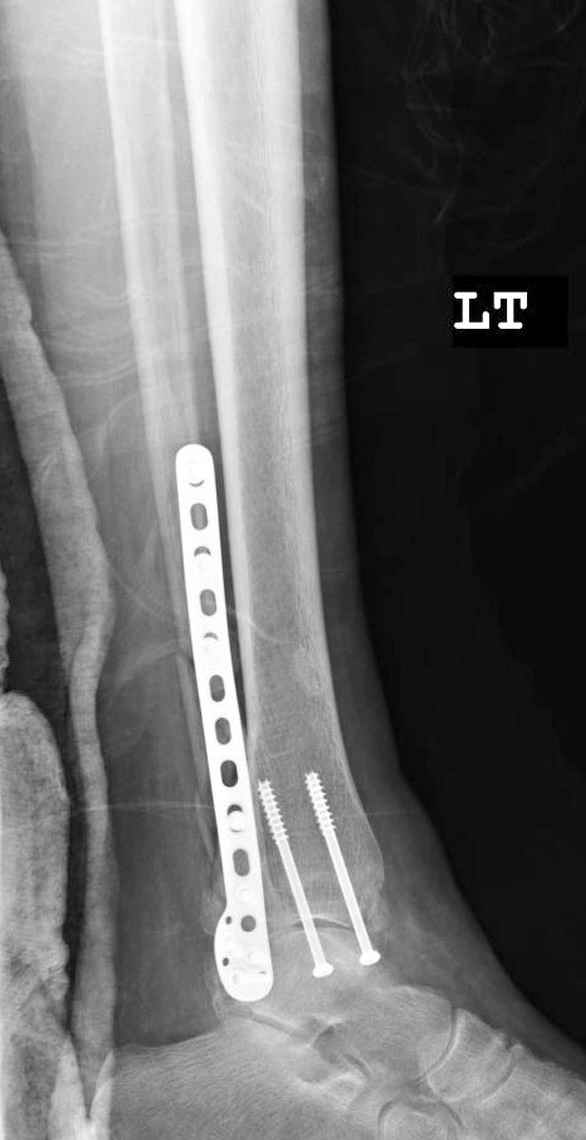

СМ> Получилось вот что.

Малоберцовая выглядит коротковатой. Профиль как-то мутный. Вообще, неплохо было бы сделать снимки в сравнении со здоровой.

> Малоберцовая выглядит коротковатой. Профиль как-то мутный. Вообще,

> неплохо было бы сделать снимки в сравнении со здоровой.

> Малоберцовая выглядит коротковатой. Профиль как-то мутный.

Конечно, малоберцовая укорочена, надо сделать косой - мортиз снимок, тогда будеть понятно, на сколько.